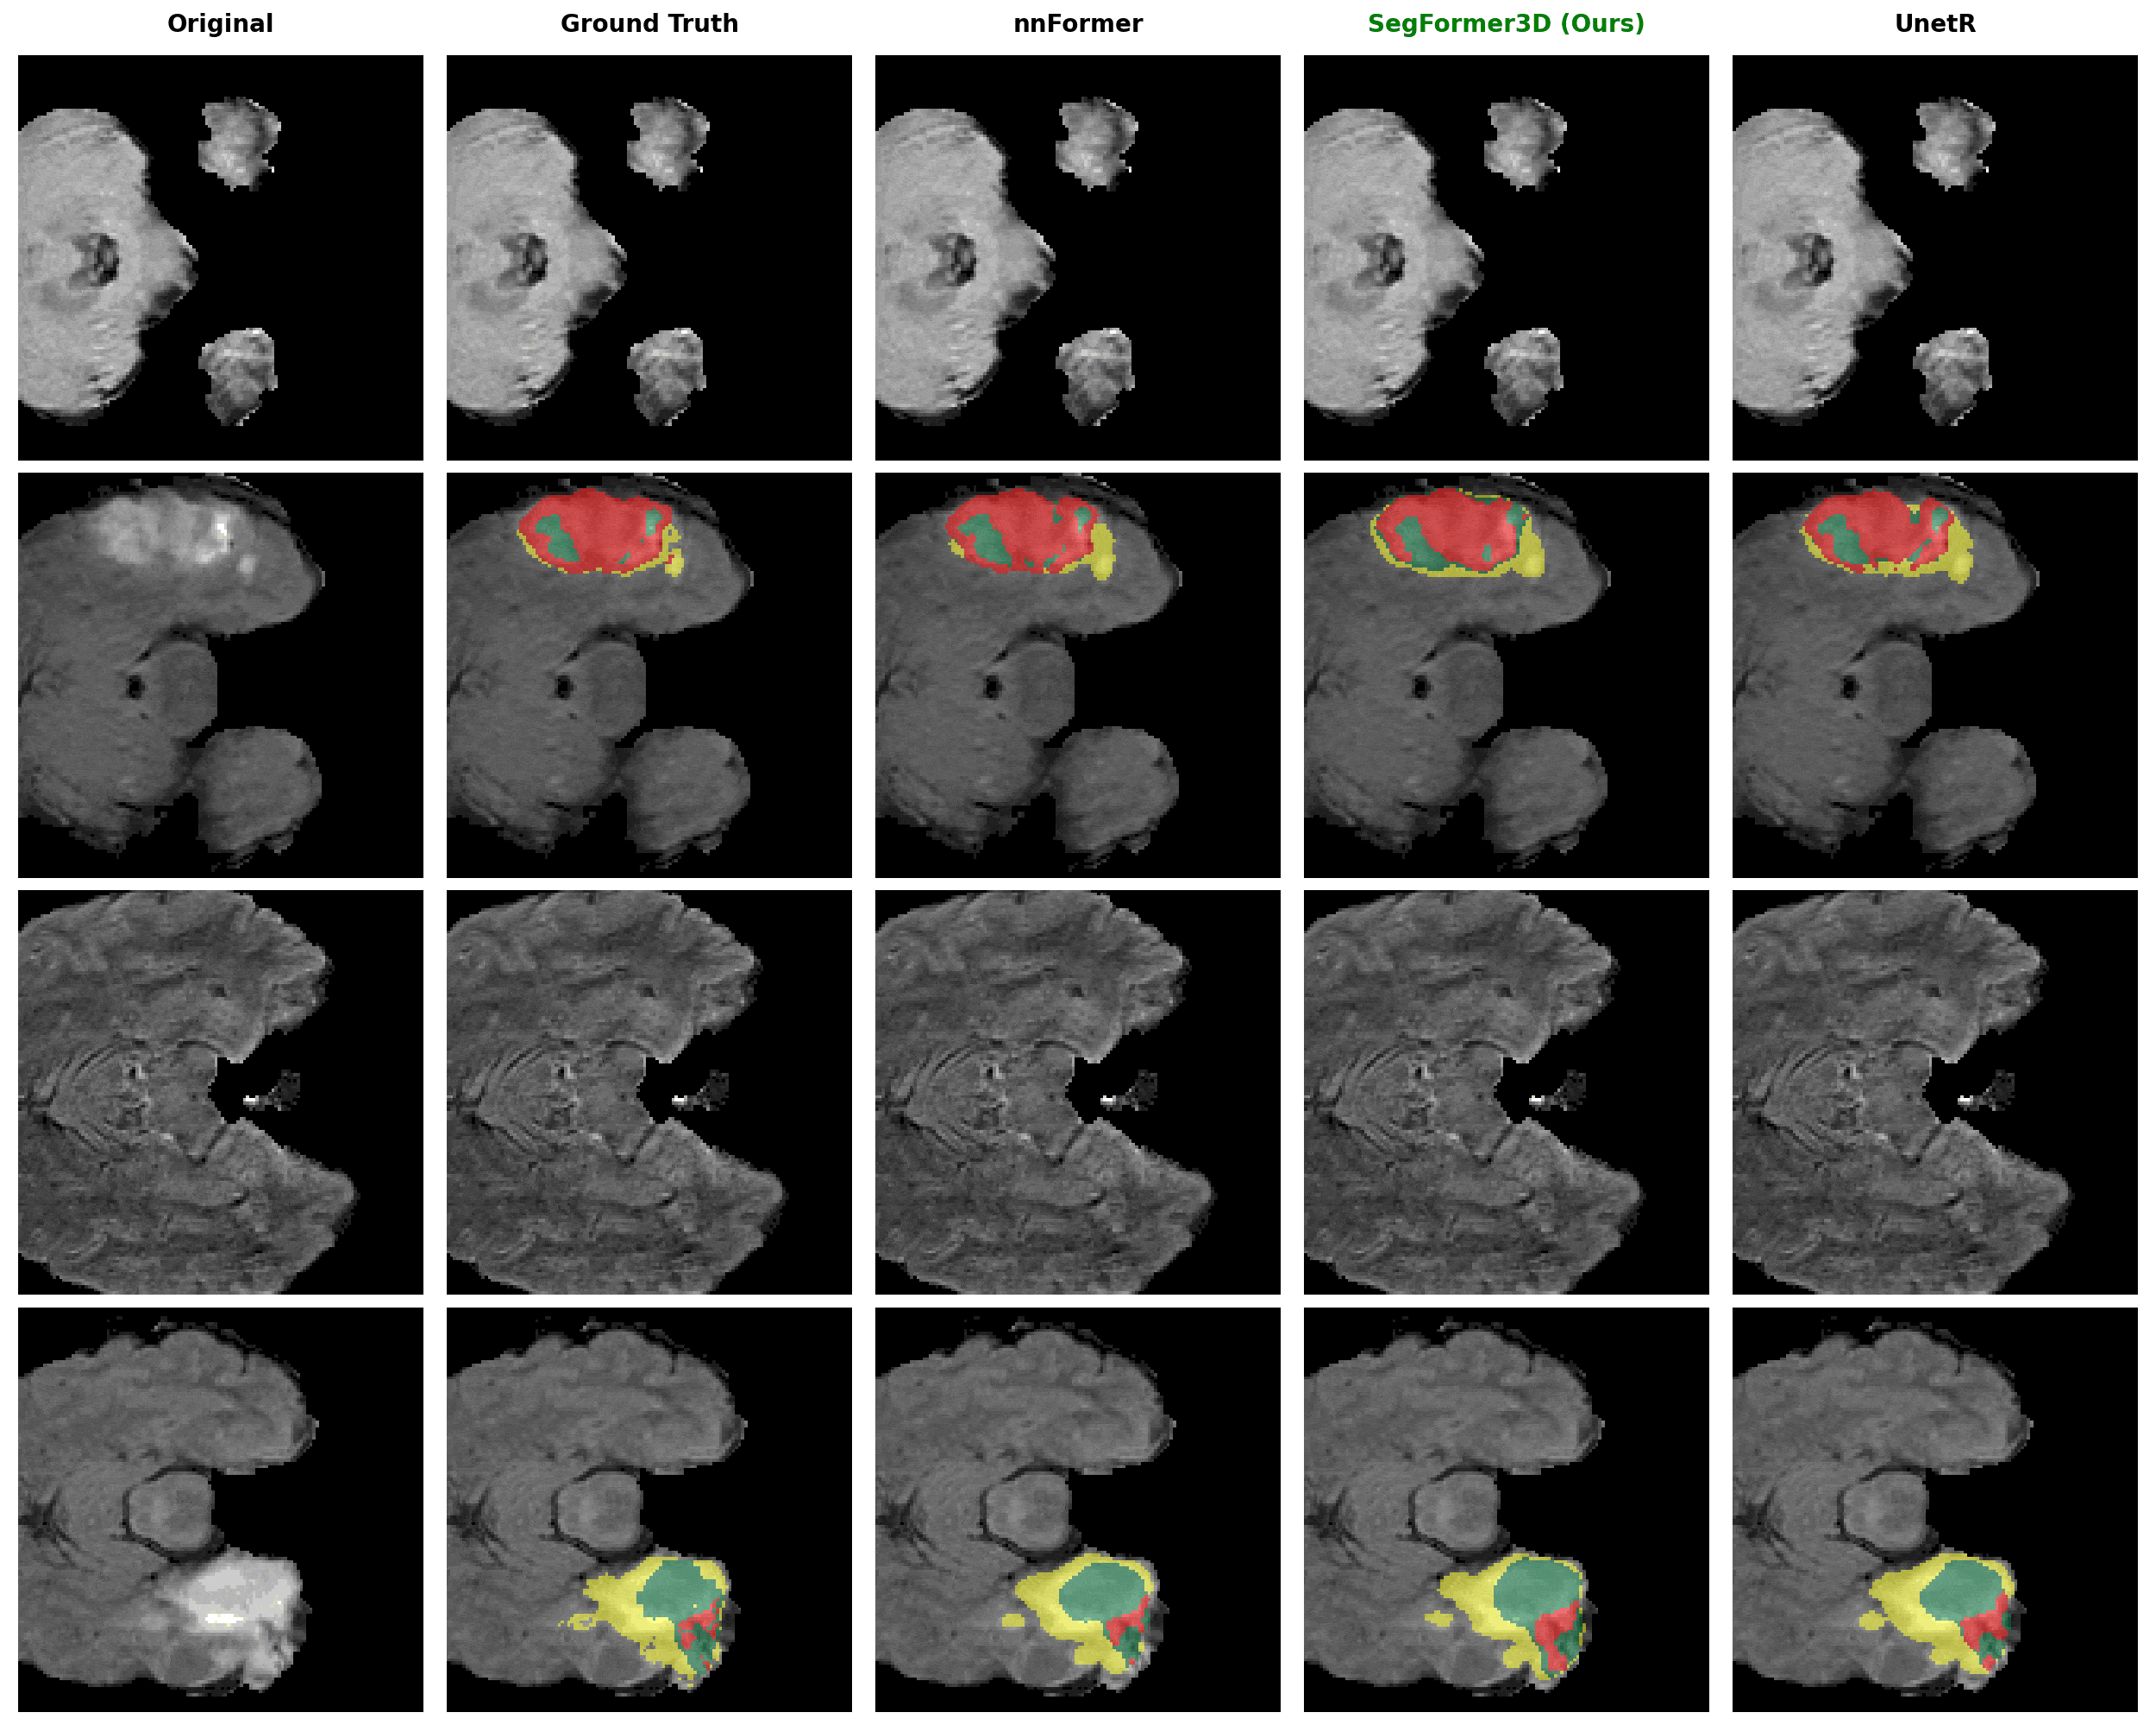

Qualitative Results

We compare SegFormer3D (highlighted in green) against state-of-the-art baselines on three medical imaging datasets. Despite being significantly lighter, our model produces highly accurate segmentation masks across all datasets.

Brain Tumor Segmentation (BRaTS)

Segmentation of tumor regions (Whole Tumor, Enhancing Tumor, Tumor Core) from multi-modal MRI scans.

BRaTS Segmentation Results